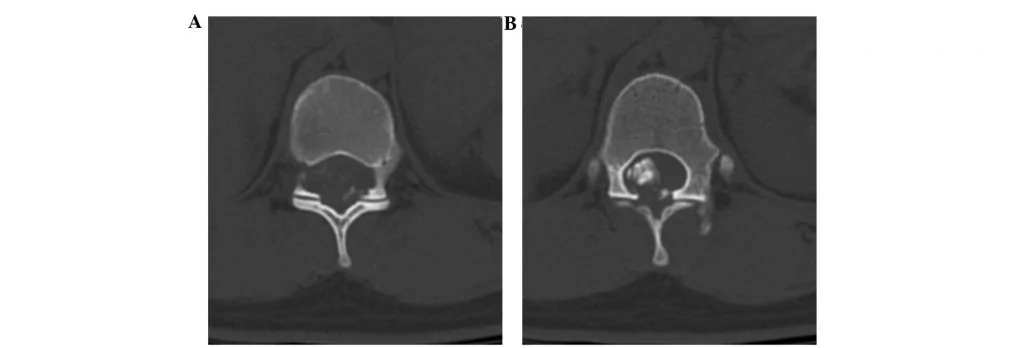

Экстрамедуллярные ОСМ могут иметь экстрадуральную (31,5%) или интрадуральную (68,5%) локализацию. Экстрамедуллярно-экстрадуральный вид отличается крупными размерами и преобладанием злокачественных форм, в свою очередь злокачественный очаг прогрессирует довольно интенсивными темпами и преимущественно распознается как вторичное (метастатическое) образование. Экстрамедуллярно-интрадуральный тип патологии, он же самый распространенный, характеризуется преобладанием первичных неврином (40%) и менингиом (25%).

- Менингиома (арахноидэндотелиома) представляет собой доброкачественную опухоль, которая растет медленно и постепенно. Образуется из клеток арахноидальной мозговой оболочки. Диагностируется в возрасте старше 50 лет, причем в преобладающем количестве у женщин (в 80%). С высокой частотой поражает спинальную оболочку в грудном отделе. Редко, но способна рецидивировать и давать множественный рост, вызывать поперечное повреждение СМ. Хоть и размер данной неоплазии, внешне напоминающей небольшой плотный узел, редко когда увеличивается более чем на 1,5 см, такая опухоль и в несколько миллиметров способна конкретно давить на нервные структуры, провоцируя суровую неврологическую клинику симптомов.

- Невринома (шваннома) – округлой формы доброкачественная ОСМ с четкими границами и плотной структурой, которая развивается в результате метаплазии леммоцитов (шванновских клеток), а именно вспомогательных клеток периферического нервного волокна, участвующих в образовании миелиновой оболочки. Пациенты женского пола чаще сталкиваются с таким недугом, наибольшую предрасположенность имеют люди средней возрастной группы и старше. Поначалу заболевание протекает скрыто, а в дальнейшем выражается сильной корешковой болью, парезами и параличом мускулатуры в области иннервации, утратой чувствительности по проводниковому типу. Шея и грудной отдел – распространенные зоны, которые поражают невриномы.